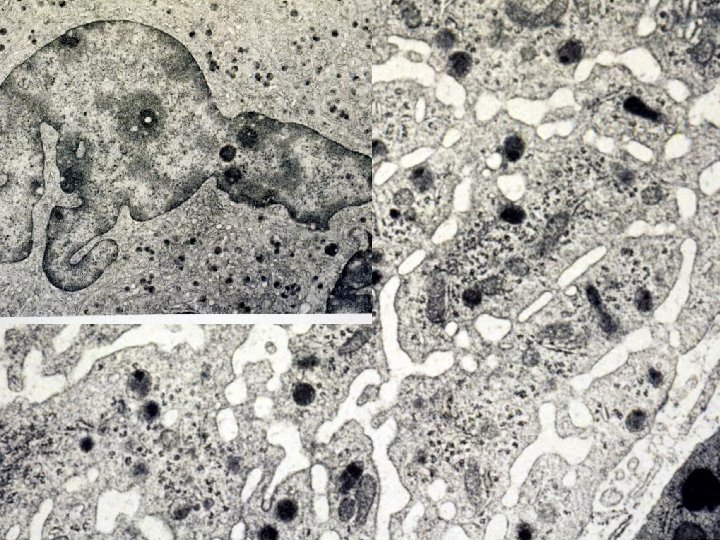

EM 6

Plasma cells

EM of white blood cells EM 8 f